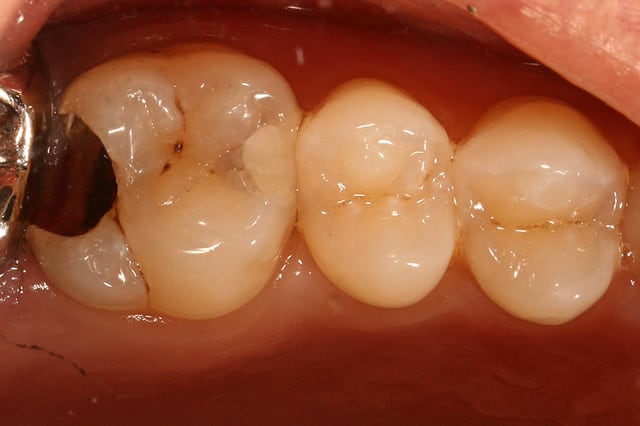

Voici l’exemple d’un cas fait comme ça hier, un cas un peu limite puisque j’ai presque pu passer avec une matrice et un coin classique, mais je n’arrivais pas à bien sertir la marge pour être étanche. On peut rattraper des trucs plus sous gingivaux que ça avec ces matrices bananes.

Pr  op 1 copy i9xxjl - Eugenol

Post op 1 copy a3l6hs - Eugenol

1 d pose amalgame crerjc - Eugenol